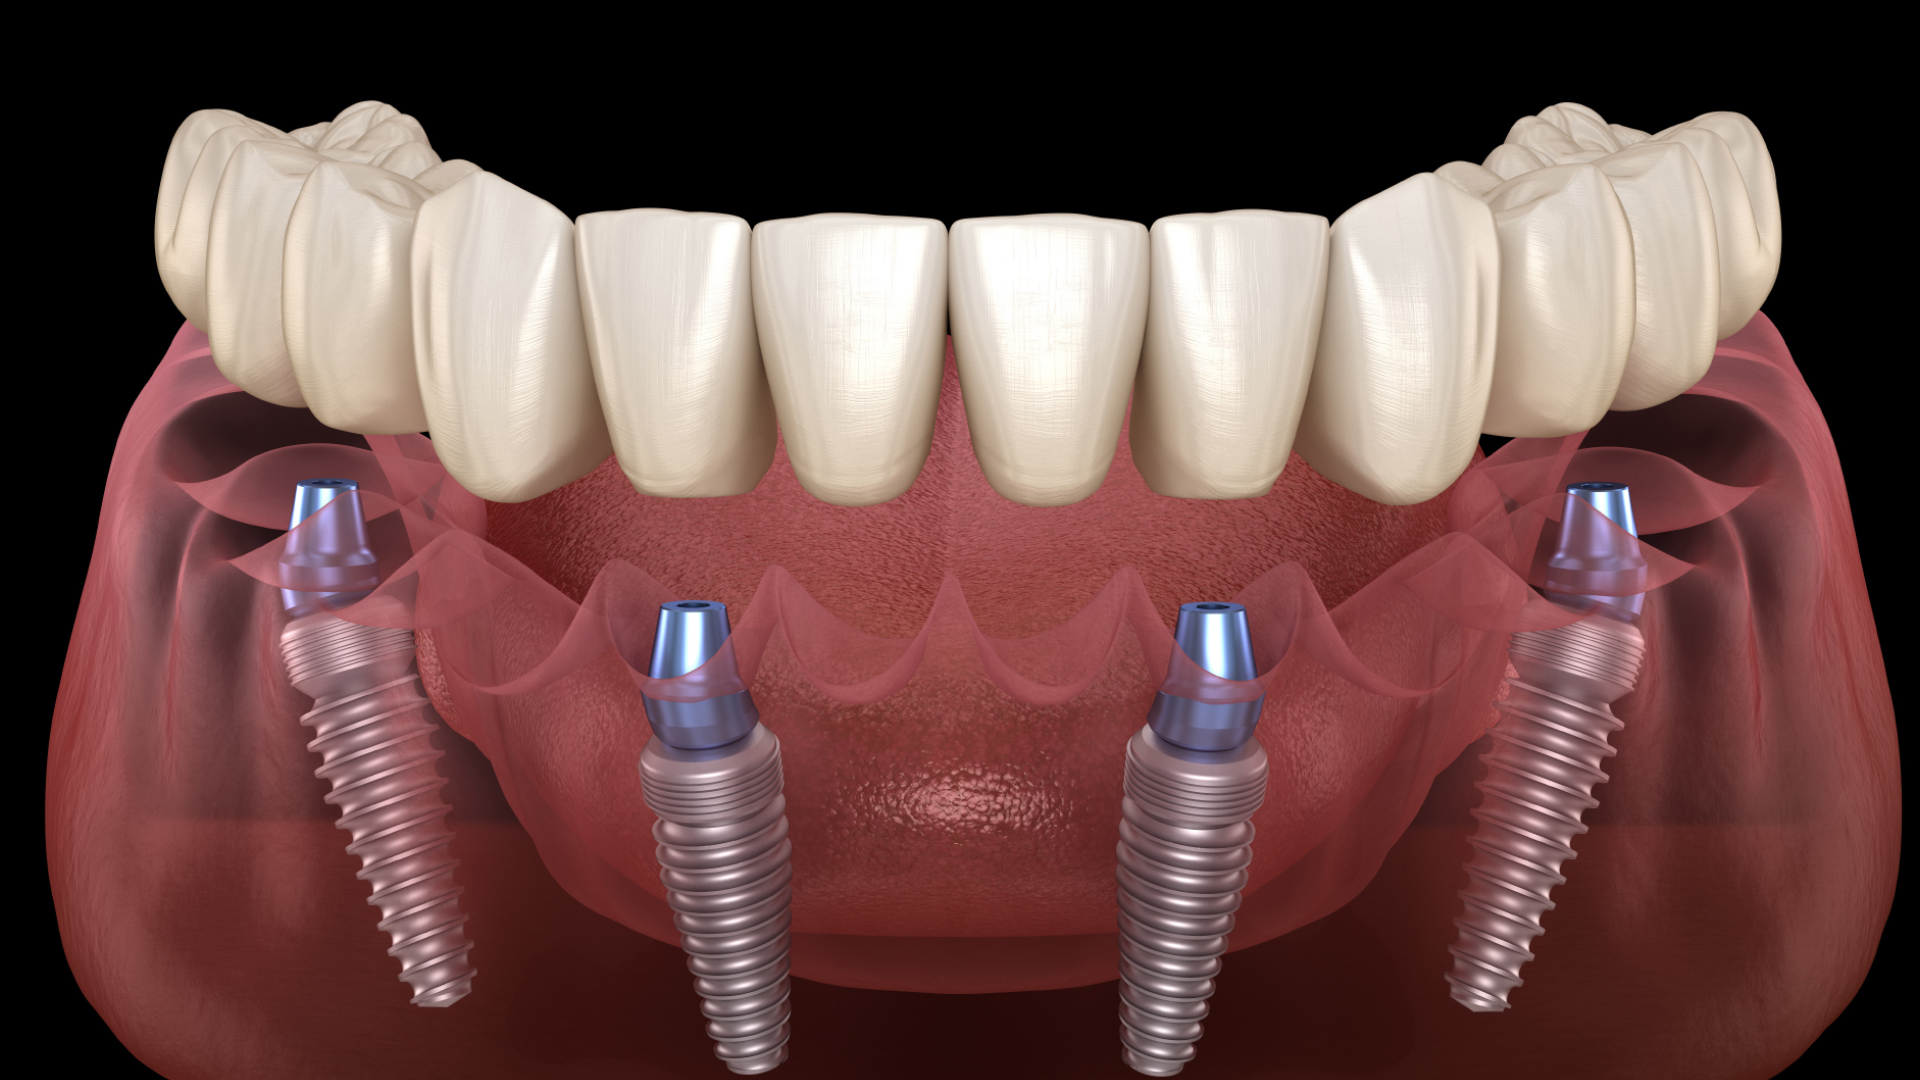

1. Sistem implant all on 4 :

4 implante + 4 multiunit+4 bonturi + 10 coroane provizorii PMMA 15.000 ron

3.000 eur

Oferta primaverii !

1. Sistem implant all on 6

6 implante + 6 multiunit+6 bonturi + 12 coroane provizorii PMMA 22.000 ron

4.400 eur

1.Implant dentar + bont +coroana metalo ceramica 3550 ron

2.Implant dentar + bont + coroana zirconiu frezata CADCAM 4000 ron